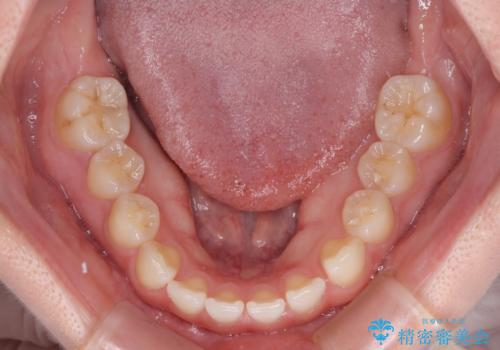

口腔内の状況を確認したところ、左右ともに下顎第二大臼歯が欠損しており、咬み合うべき上顎の第二大臼歯が著しく挺出していました。

挺出した大臼歯を元の位置に戻すことは現実的に難しいため抜歯することとし、補助装置とワイヤー装置により上顎歯列全体を後方に移動することとしました。